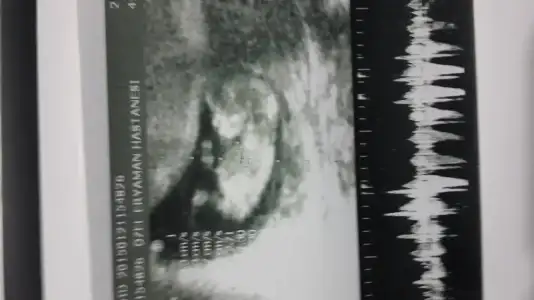

dr soylemeden siz gorun genital nub teorisi ( bebegin cinsiyeti)

Kimler kimler yazdı?zzmasalpippost: 39175201 .!.:Doktor daha belli olmaz diyor ama 3 d resmine bakar misin çıkınti var erkek mi dedim belli olmaz diyor.ama ben çok kız istiyorum.

Evet bu 3d de pipi gibi bisey var kesin kiz dediğim fotoyu tekrar atarmisin canm

Canım dediğim gibi 11+1 bu dün gittim Dr A Dr yüzde 60 erkek dedi. Kız geçiyor içimden benim bir oglum var hayırlısı Allah'tan

Kac[/QUOTE]cnm bu gun doktora gittim 11+1 gunluk doktor bir cikinti var erkek olabilir dedi

ben erkege benzettim canim Allah gonlune gore versin insallah..

cnm benim bebegim icinde bir yorumda bulunabilirmisin[/QUOTE]ben erkege benzettim canim Allah gonlune gore versin insallah..

Cok kucuk bu minik annesi ama kiza benzettim gibi emin degilim bende kendimce tahmin ediyorum Hayirlisi hakkinda insallah

cok tskler cnm buda diger fotosu doktor cikinti var kordon degilse erkek dedi